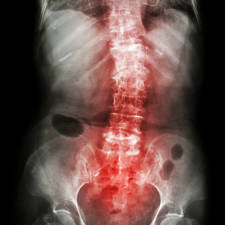

En este artículo os contaremos como se inicia la degeneración del disco intervertebral y las consecuencias de esta degeneración, la discopatía.

El dolor de espalda afecta al 80% de las personas a lo largo de la vida y se estima que el 40% del dolor lumbar tiene como origen el disco intervertebral.

¿Qué es una discopatía degenerativa?

Entendemos como discopatia degenerativa a los cambios que se producen en el disco intervertebral relacionados con el tiempo y como consecuencia la pérdida de la función que desarrollaba.

Cuando un disco intervertebral comienza a degenerarse van a aparecer una serie de cambios en su estructura que derivan en la pérdida de función y la aparición del dolor.